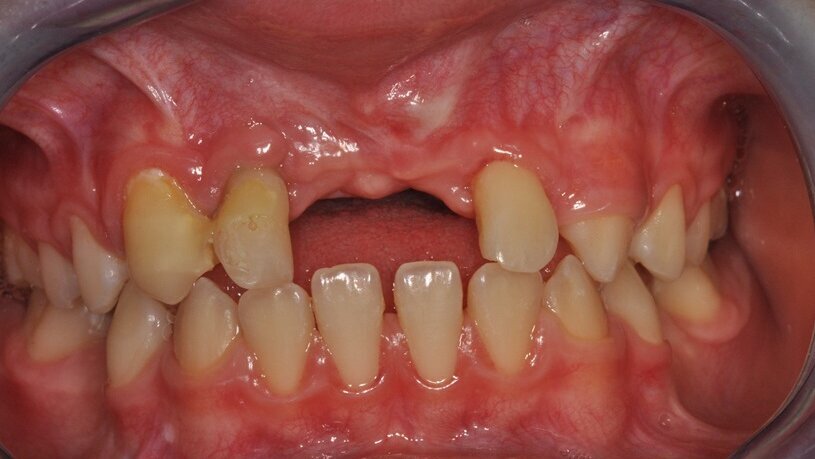

W dniu wizyty w poradni brak było oznak ostrego stanu zapalnego w okolicy 12-11. Widoczne były recesje dziąsła o wysokości 2 mm po stronie wargowej na zębach siecznych górnych przyśrodkowych, zmniejszona wysokość dziąsła zrogowaciałego do wartości 2 mm, spłycony przedsionek (Ryc. 1). Zęby były tkliwe na opukiwanie pionowe i poziome oraz wykazywały I stopień rozchwiania wg Entina. W przekrojach TK widoczny był rozległy przewlekły stan zapalny wokół wierzchołków korzeni zębów 11 i 21 (Ryc. 2), brak blaszki przedsionkowej wyrostka zębodołowego szczęki oraz resorpcja korzeni. Po wnikliwej analizie stanu miejscowego i rozmowie z rodzicami zadecydowano o ekstrakcji zębów 11 i 21 oraz w drugim etapie, ze względu na rozległy i zaawansowany proces zapalny, o autotransplantacji zawiązków 35 i 45.

Ryc. 1_Stan miejscowy przed ekstrakcja zębów 11 i 21.